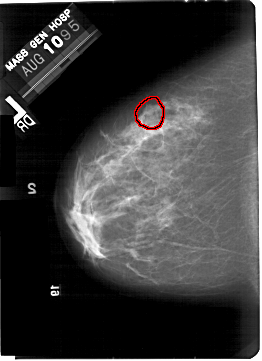

A_1445_1.LEFT_MLO

LEFT_MLO LINES 5491 PIXELS_PER_LINE 3916 BITS_PER_PIXEL 12 RESOLUTION 43.5 OVERLAY

FILE: A_1445_1.LEFT_MLO.OVERLAY

TOTAL_ABNORMALITIES 1

ABNORMALITY 1

LESION_TYPE MASS SHAPE ROUND MARGINS OBSCURED

ASSESSMENT 3

SUBTLETY 2

PATHOLOGY BENIGN

TOTAL_OUTLINES 1

BOUNDARY